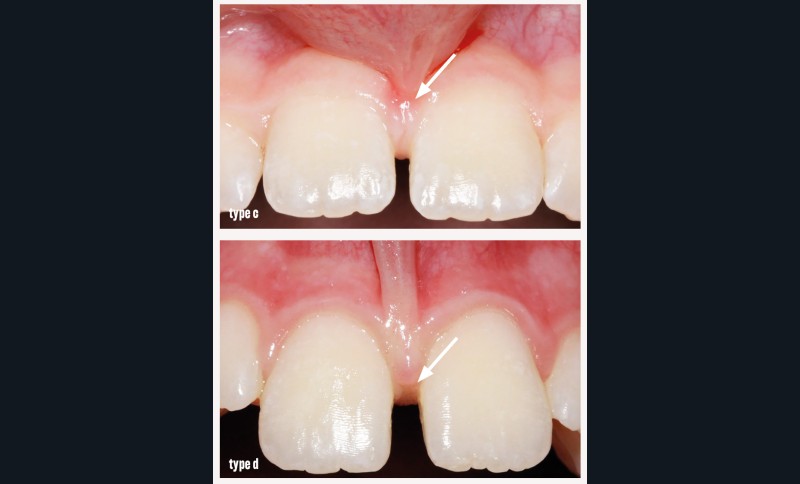

• type c : frein avec une insertion au niveau de la gencive papillaire ;

• type d : frein interdentaire avec une insertion qui rejoint la papille bunoïde.

Généralement, l’indication parodontale des freinectomies concerne le type c avec mobilisation de la gencive marginale et le type d.